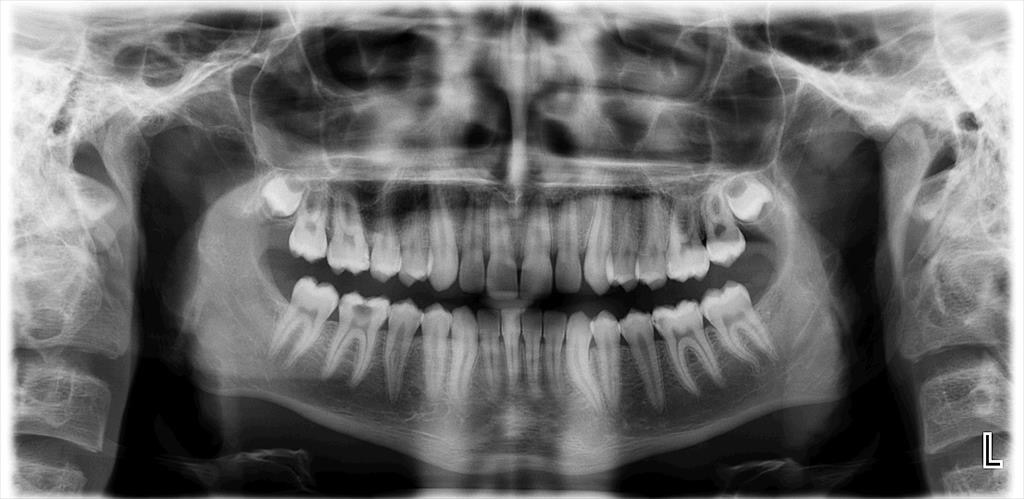

The diagnosis of AP was confirmed by clinical and radiographic examinations. All types of AP, including asymptomatic AP, symptomatic AP, acute apical abscess, and chronic apical abscess were considered. All radiographic images were obtained using the same imaging system (Planmeca Promax; Planmeca, Helsinki, Finland). If the periapical tissue was normal or had minimal changes in bone structure, the related tooth was classified as healthy (PAI 1 and 2), according to the periapical index (PAI).19 In the event of a lost periodontal ligament or periodontitis with exacerbating features (PAI 3, 4 and 5), the tooth was classified with a periapical pathology.20 The PAI score for multi-rooted teeth was determined based on the highest score observed across all roots.21

Digital panoramic radiographs were taken and analyzed by an endodontist and an experienced dentist (Figure 1,Figure 2). Both observers were blinded to the study groups. In cases of disagreement, the analysis was repeated. After the radiographic analysis, pulp sensitivity, percussion and palpation tests were performed to confirm the clinical diagnosis of AP. Patients with at least 1 tooth exhibiting signs of AP were included in the AP group.